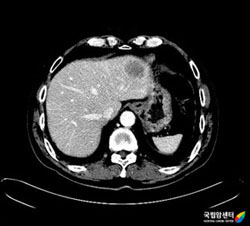

전산화단층촬영(CT)은 항문암 자체의 진단, 인접 장기 및 멀리 있는 장기 (예: 간, 폐), 림프절로의 전이 여부 등을 규명하는데 사용됩니다. 전산화단층촬영(CT)은 국소부위에 종양 확산 정도를 평가하는데 도움을 주며, 특히 종양이 주변 조직이나 다른 장기를 침범했을 가능성이 있을 때 진단에 더욱 도움을 줍니다. 간이나 폐, 림프절 등으로의 전이 여부를 검사할 때 가장 널리 사용되는 방법입니다.

[ 간으로 전이된 항문암의 CT 소견 ]

보통의 전산화단층촬영(CT)을 위해서 전날은 특별한 처치를 필요로 하지 않고, 다만 검사 당일 8시간 정도의 금식이 필요합니다. 전산화단층촬영(CT)을 시행하는 동안 환자는 정맥주사를 통해서 조영제를 주입받은 후에 검사를 받습니다. 이때, 콩팥의 기능이 떨어져 있는 환자나 이전에 조영제에 알레르기 반응, 즉 조영제 주입 후 심한 구토, 발적, 두드러기, 가려움증, 목이 붓고 쉬는 듯한 증상을 보인 적이 있는 환자는 전산화단층촬영(CT)을 시행하기 전에 담당 의사와 상의해야 합니다.